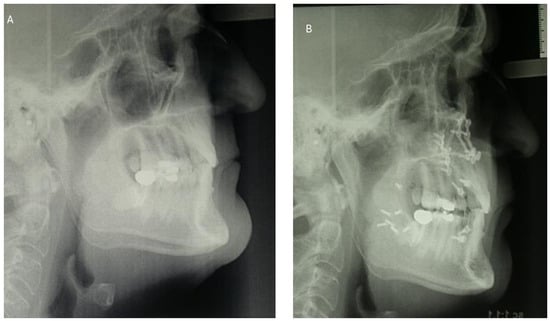

3.1.3. Cephalometric Changes Following Orthognathic Surgery

3.2.3. Cephalometric Changes Following Orthognathic Surgery